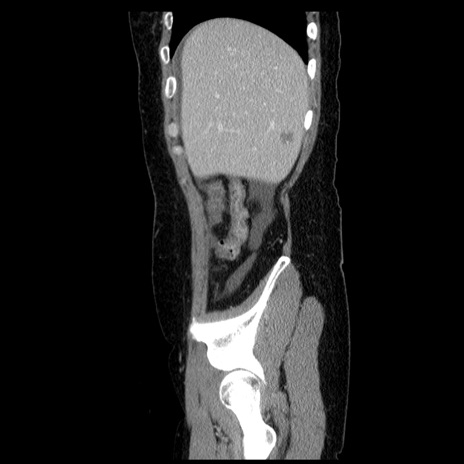

症例6(矢状断像)

冠状断像